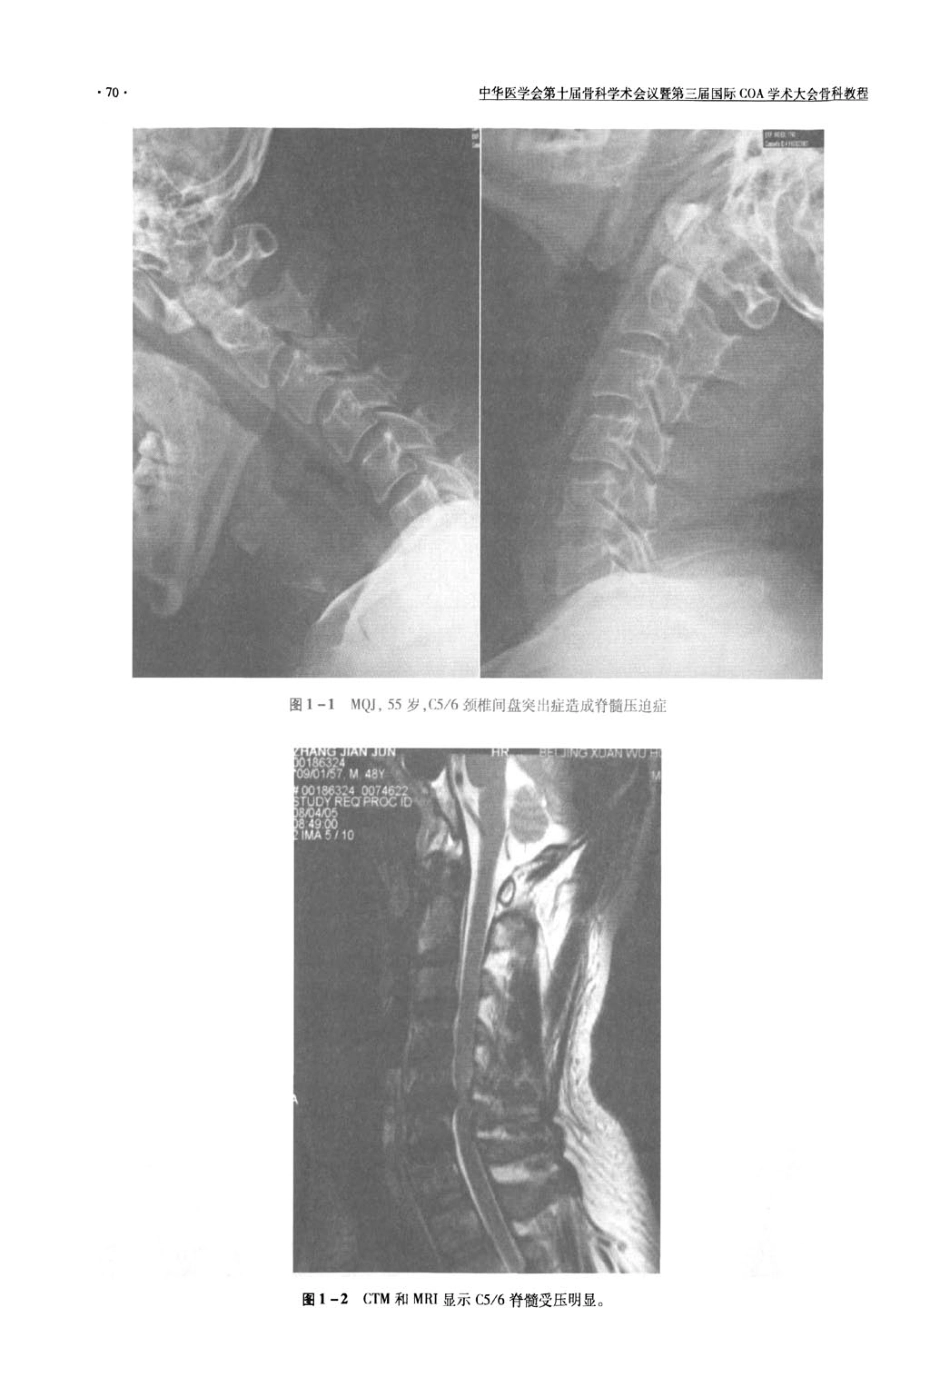

68生生Ⅸ生魁臣]尘盘烈生盘会丝暨堑二堕咀睦业&芏芷丝删煎型果进步三等奖”。田伟北京积水潭医院院长,脊柱外科主任,教授、博士生导师。中华医学会骨科分会常委;脊柱外科学组副组长;北京医学会骨科学专业委员会主任委员;北京市创伤骨科研究所所长,全国计算机辅助外科学会主任委员;中国青年科技工作者协会副会长;中国残联脊柱脊髓损伤委员会副会长;中华医学会创伤学会委员;北京市突贡专家.中央保健局会诊专家;享受国务院“政府特殊津贴”专家;美国骨科学会会员。拳与出版著作6部,发表论文30余篇.专利1项曾获“北京市科技成颈椎人工间盘置换手术日楠北京积水潭医院北京是学第四临床医学院脊柱外科。概蜕自从50年代Smith-Robins(m和Cbward等的颈椎前路融合于术被广泛血用以来,这种手术形止成为r最为标准的领椎手术之-o以覃】:很多医生忘记丁这种r术本身斗水足生帕蛀韧目的。颈椎F术的根术口的是为了解除神经压迫,解除疼痛,恢复稳定性。但足,都不是希嘤破坷、颈椎术身的生理功能,或青说希掌通过手术恢复止掉的牛理功能。丁H是过去确是个梦想中椎以达到的口标,H打融台手术枉牺牲r秆柱正常的可动陛之后起到r桦除疼痛,稳定脊柱的忭川。但是融☆手术带来的不照副作用也是硅『M易她们,使{导颈椎的整体活动范Ⅲ明显受限.融合风r下的椎问隙m于应力集一l一而损害叫显,越盘压地神经需要进行一次下术cHilibrand等发现颈椎60路融合手术后每年有29%的融台邻近Iq隙山删问题。如何避免融台下术,保持颈椎手术mJ隙的rⅡ动胜一育足被探索的谍题。进行椎间人上问盘胃换的探索的历史并不足很长。首先进行尝试的是在腰椎问盘。FemstmmA1966介纠了使}IIA<锈钢球状人】:问盘在磴椎秩痫的治疗经验二他也在钡批进行了战用。Cummins等人也设汁rH样的人r颈椎问靠领椎人』二椎问盘的设计有两个级别的n标I初缎H标:设i【戚硬性的球形关节,可以构成各个方向的活动,并且呵“阿定枉椎体上。2高缄目标:进步模拟自然椎问盘.可以达成瞬时运动中心.具打滑动,而且r,f眦有弹什,【烂收负荷传导的压力。目前可以在临床上使用的人T:椎l刊盘多数j{能到初级目标,少数增加了一定滑动。Bryan颤椎人I:问盘是一种可咀达到高级目标的人1.椎q盘,足在2002年椰2003年自先被Bt?;an抖{告的。Bryan人上椎间盘假体采用钛合金外壳和有弹性的聚氯酯髓核构成。假体上下终扳接触面有珊瑚样钛微孔涂层利于哥长入,外层有全封闭半透膜的封套,避免有碎屑溢出,是为r醯少造成松动的州素。A.T.faJ盘提供备方向11度活动.2mm滑动。有弹性可适当旋转,我们在2003年12月进行r第一例I]ryan颈椎人上问盘置换手术,以后到200年我们完成了22】例.267个间盘嚣换。男性I35蜘,女性86例。单阶段置换179例,双阶段38例,二阶段4例。术后JOA政善率达到473%,3年以后随访达到"5%,5F36达到765分;Odom’s评分良好以f达到971%,NDIl4分以r者达到704%,VAS达到935%满意牢。3年以上病例的置换问隙活动达到术前的846%,临近间隙活动达到833%,颈椎前凸曲线_手【|术前相比略有F降,术前甲均109度,3年后平均9度,有统计学差异。术后n“生堡医堂金筮土屋盟越堂垄金丝墅蓥三届国匾!Q皇堂丕左金盈叠熬猩有5例发生明显的HO,造成置换间隙活动降低或消失,主要原因是置换间盘型号小和术前没有判断出来的OPLL病例。下沉和松动的只是发生l到2例,没有需要再次手术的病例,长期随访效果让人满意。二、手术适应症人工间盘置换的手术适应症,除了各种原因的颈椎不稳定外,基本是过去前路融合手术适应的病例。但是值得讨论的是,原来单阶段压迫,但是临近间隙已经明显退变的病例融合选择融合节段比较困难,人工间盘由于可动,对临近间隙的影响很小,反而容易决定,只是进行压迫间隙的减压置换就可以了。具体适应症如下:(1)颈椎间盘突出症。(2)颈椎病的单阶段或双阶段压迫脊髓或神经根,或明确造成顽固的交感神经型颈椎病的阶段。但是如果椎体中部也存在椎管狭窄的病例应该除外。三个节段及以上的问题应该比较慎重,一是因为广泛阶段的压迫常常表现出明显的椎管狭窄,更适合后路的椎管扩大成形手术,另外人工间盘置换手术需要...